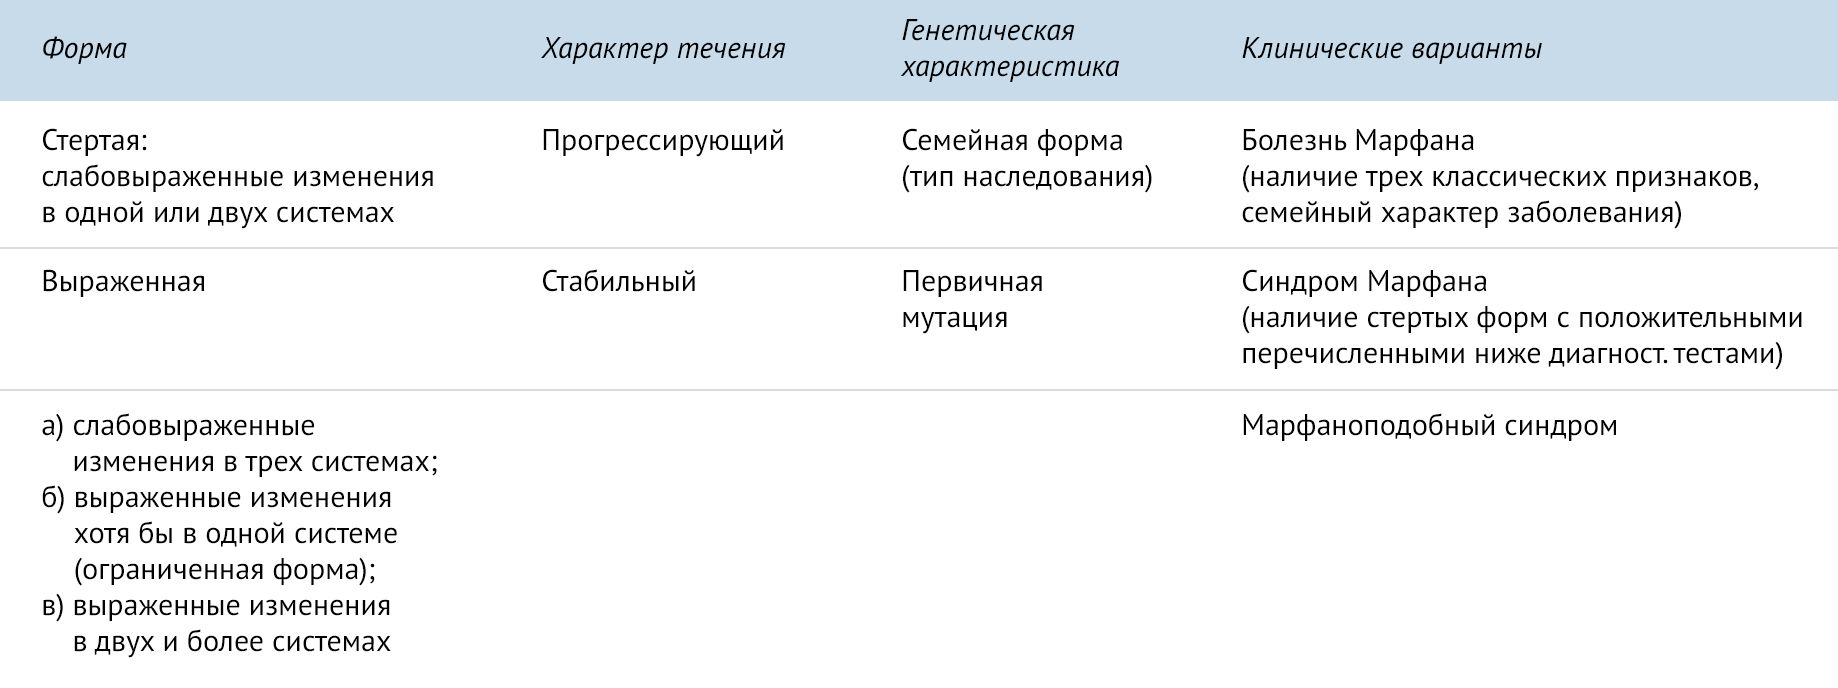

Sindrom marfana tema nauchnoj stati po klinicheskoj medicine chitajte besplatno tekst nauchno issledovatelskoj raboty v elektronnoj biblioteke kiberleninka (Тип файлу jpg)

Sindrom Marfana Tema Nauchnoj Stati Po Klinicheskoj Medicine Chitajte Besplatno Tekst Nauchno Issledovatelskoj Raboty V Elektronnoj Biblioteke Kiberleninka

Sindrom marfana tema nauchnoj stati po klinicheskoj medicine chitajte besplatno tekst nauchno issledovatelskoj raboty v elektronnoj biblioteke kiberleninka (Тип файлу jpg)

Sindrom Marfana Tema Nauchnoj Stati Po Klinicheskoj Medicine Chitajte Besplatno Tekst Nauchno Issledovatelskoj Raboty V Elektronnoj Biblioteke Kiberleninka